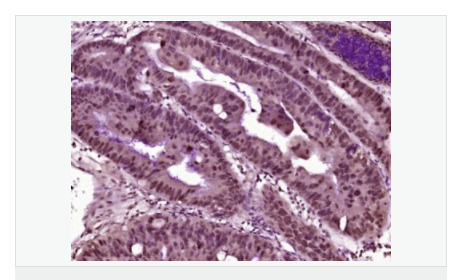

產(chǎn)品介紹The product of this gene phosphorylates the beta-2-adrenergic receptor and appears to mediate agonist-specific desensitization observed at high agonist concentrations. This protein is an ubiquitous cytosolic enzyme that specifically phosphorylates the activated form of the beta-adrenergic and related G-protein-coupled receptors. Abnormal coupling of beta-adrenergic receptor to G protein is involved in the pathogenesis of the failing heart. [provided by RefSeq].

Function:

Specifically phosphorylates the agonist-occupied form of the beta-adrenergic and closely related receptors, probably inducing a desensitization of them. Key regulator of LPAR1 signaling. Competes with RALA for binding to LPAR1 thus affecting the signaling properties of the receptor. Desensitizes LPAR1 and LPAR2 in a phosphorylation-independent manner.

Tissue Specificity:

Expressed in peripheral blood leukocytes.